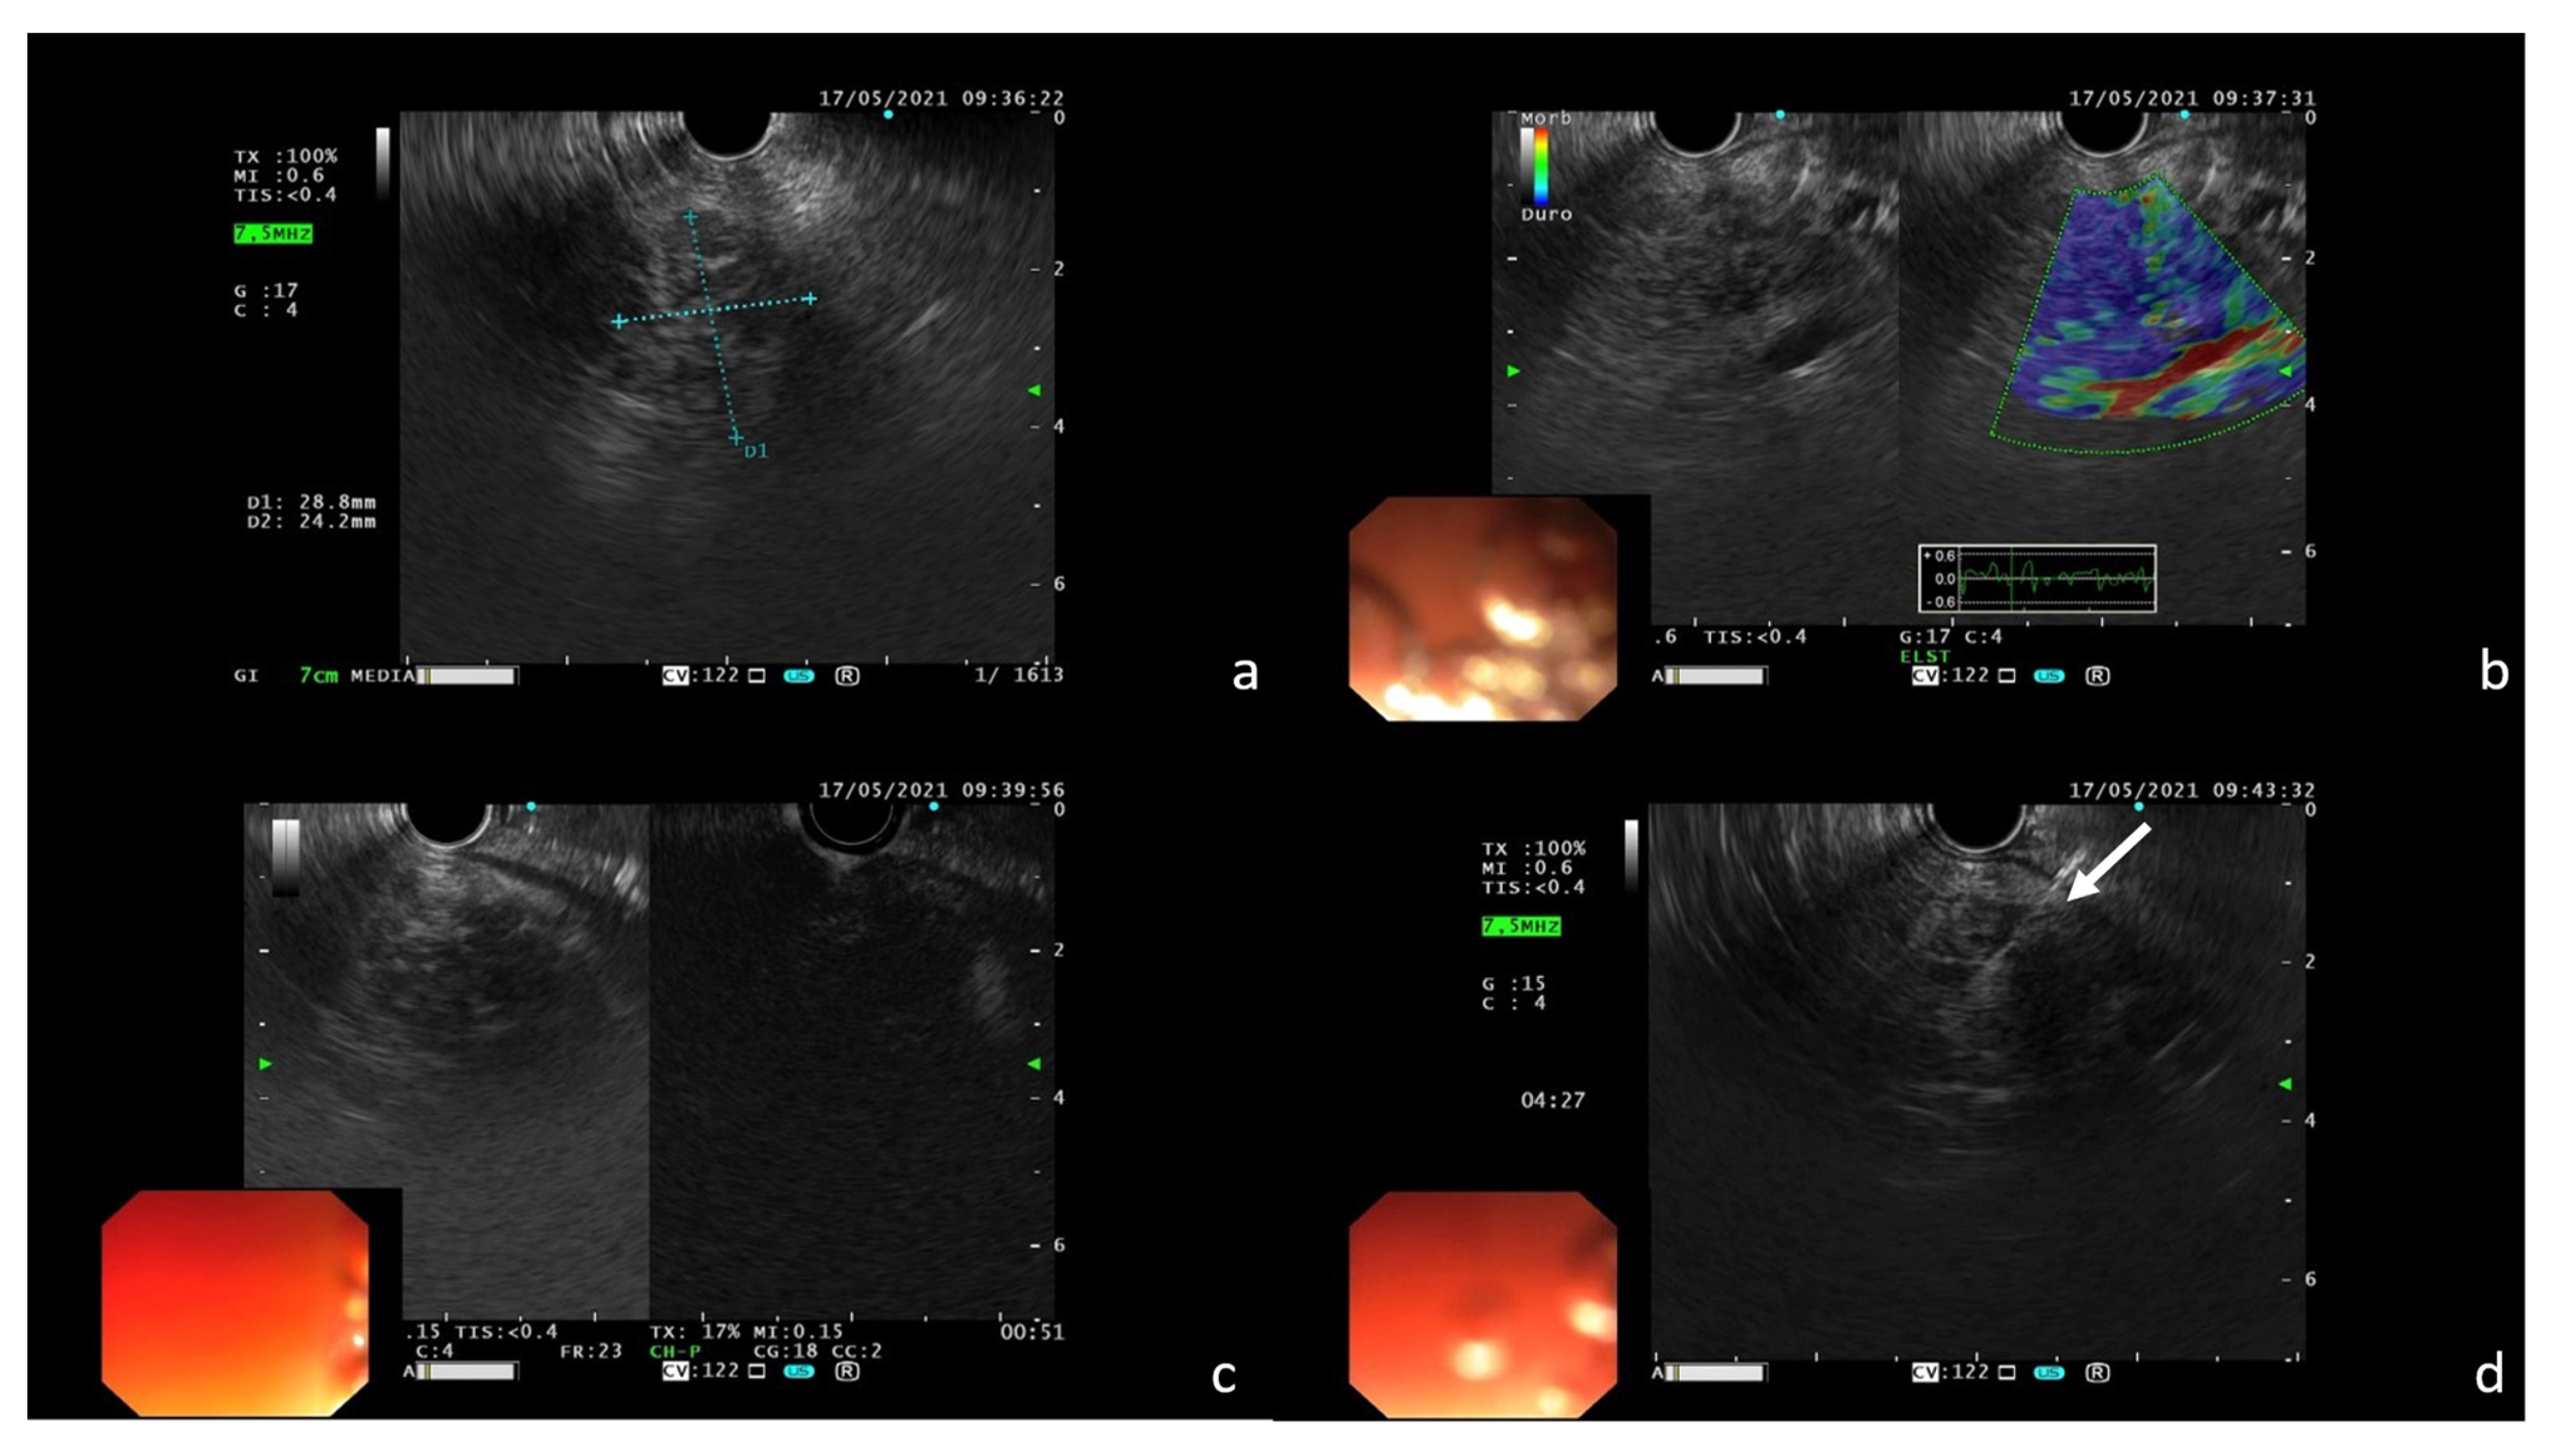

2. Case Report